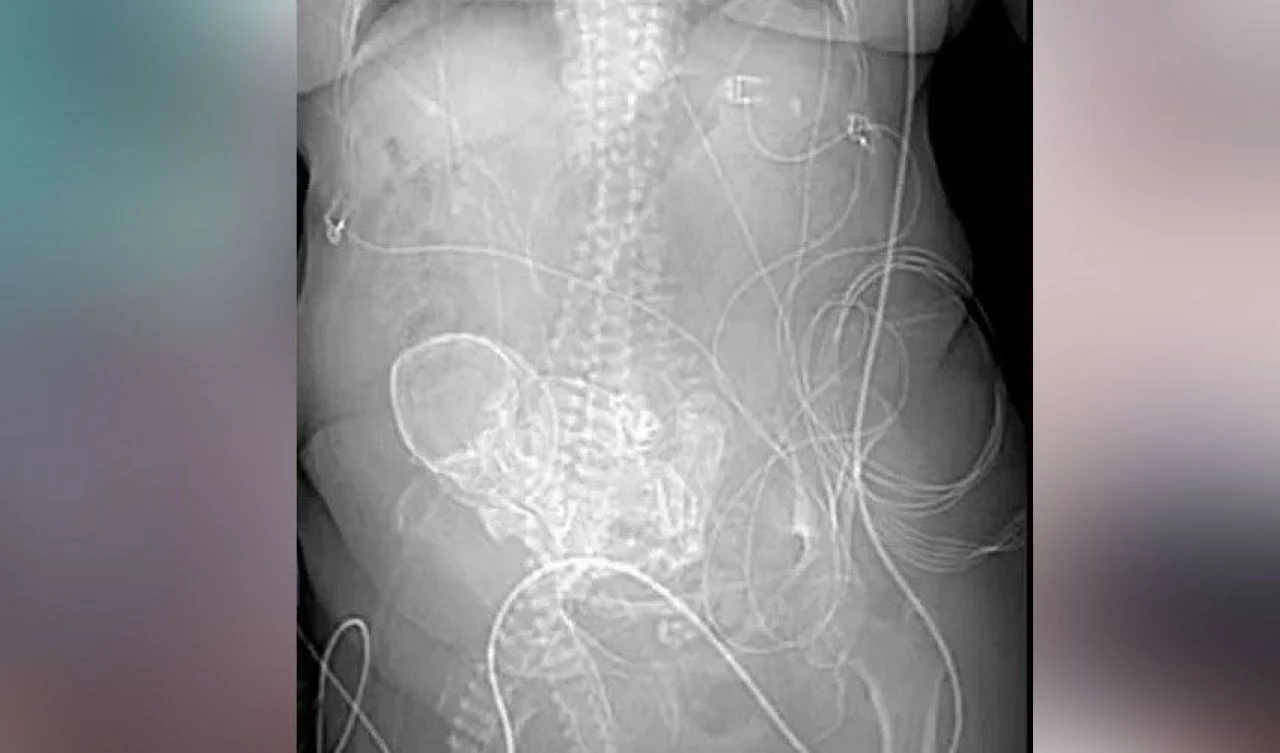

Vera için üç boyutlu bir tarama yapan doktorlar karnında kireçlenmiş bir fetüs olduğunu fark ettiler.

Nadir görülen bir durum olan 'taş bebek' hastalığıyla karşı karşıya kalan Vera, Brezilya'da acil olarak ameliyata alındı.